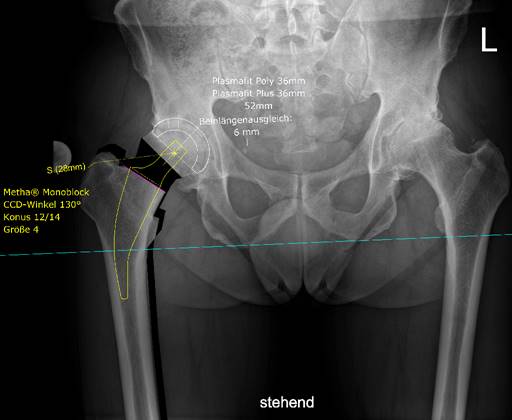

Für die Behandlung der Arthrose liegt bei uns ein besonders großer Erfahrungsschatz vor. Wir betreiben sowohl die konservative (Doppelspritze mit körpereigenen Wachstumsfaktoren und Hyaluronsäure) als auch die operative Orthopädie. Chefarzt Dr. M. Blanke ist Leiter und Hauptoperateur des zertifizierten EndoProthesenZentrums Leopoldina Schweinfurt und Mitglied der Deutschen Gesellschaft für Endoprothetik. Von der minimalinvasiven zementfreien Kurzschaftprothese mit spezieller Keramikoberfläche bis hin zur komplexen Prothesenwechseloperation und individuell hergestellten Endoprothese, sprechen unsere Operationszahlen und die Zufriedenheit unserer Patienten für sich.